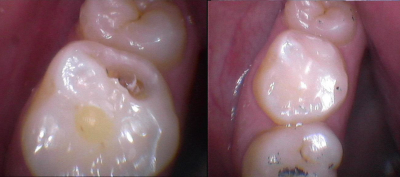

Gallery

Galeria